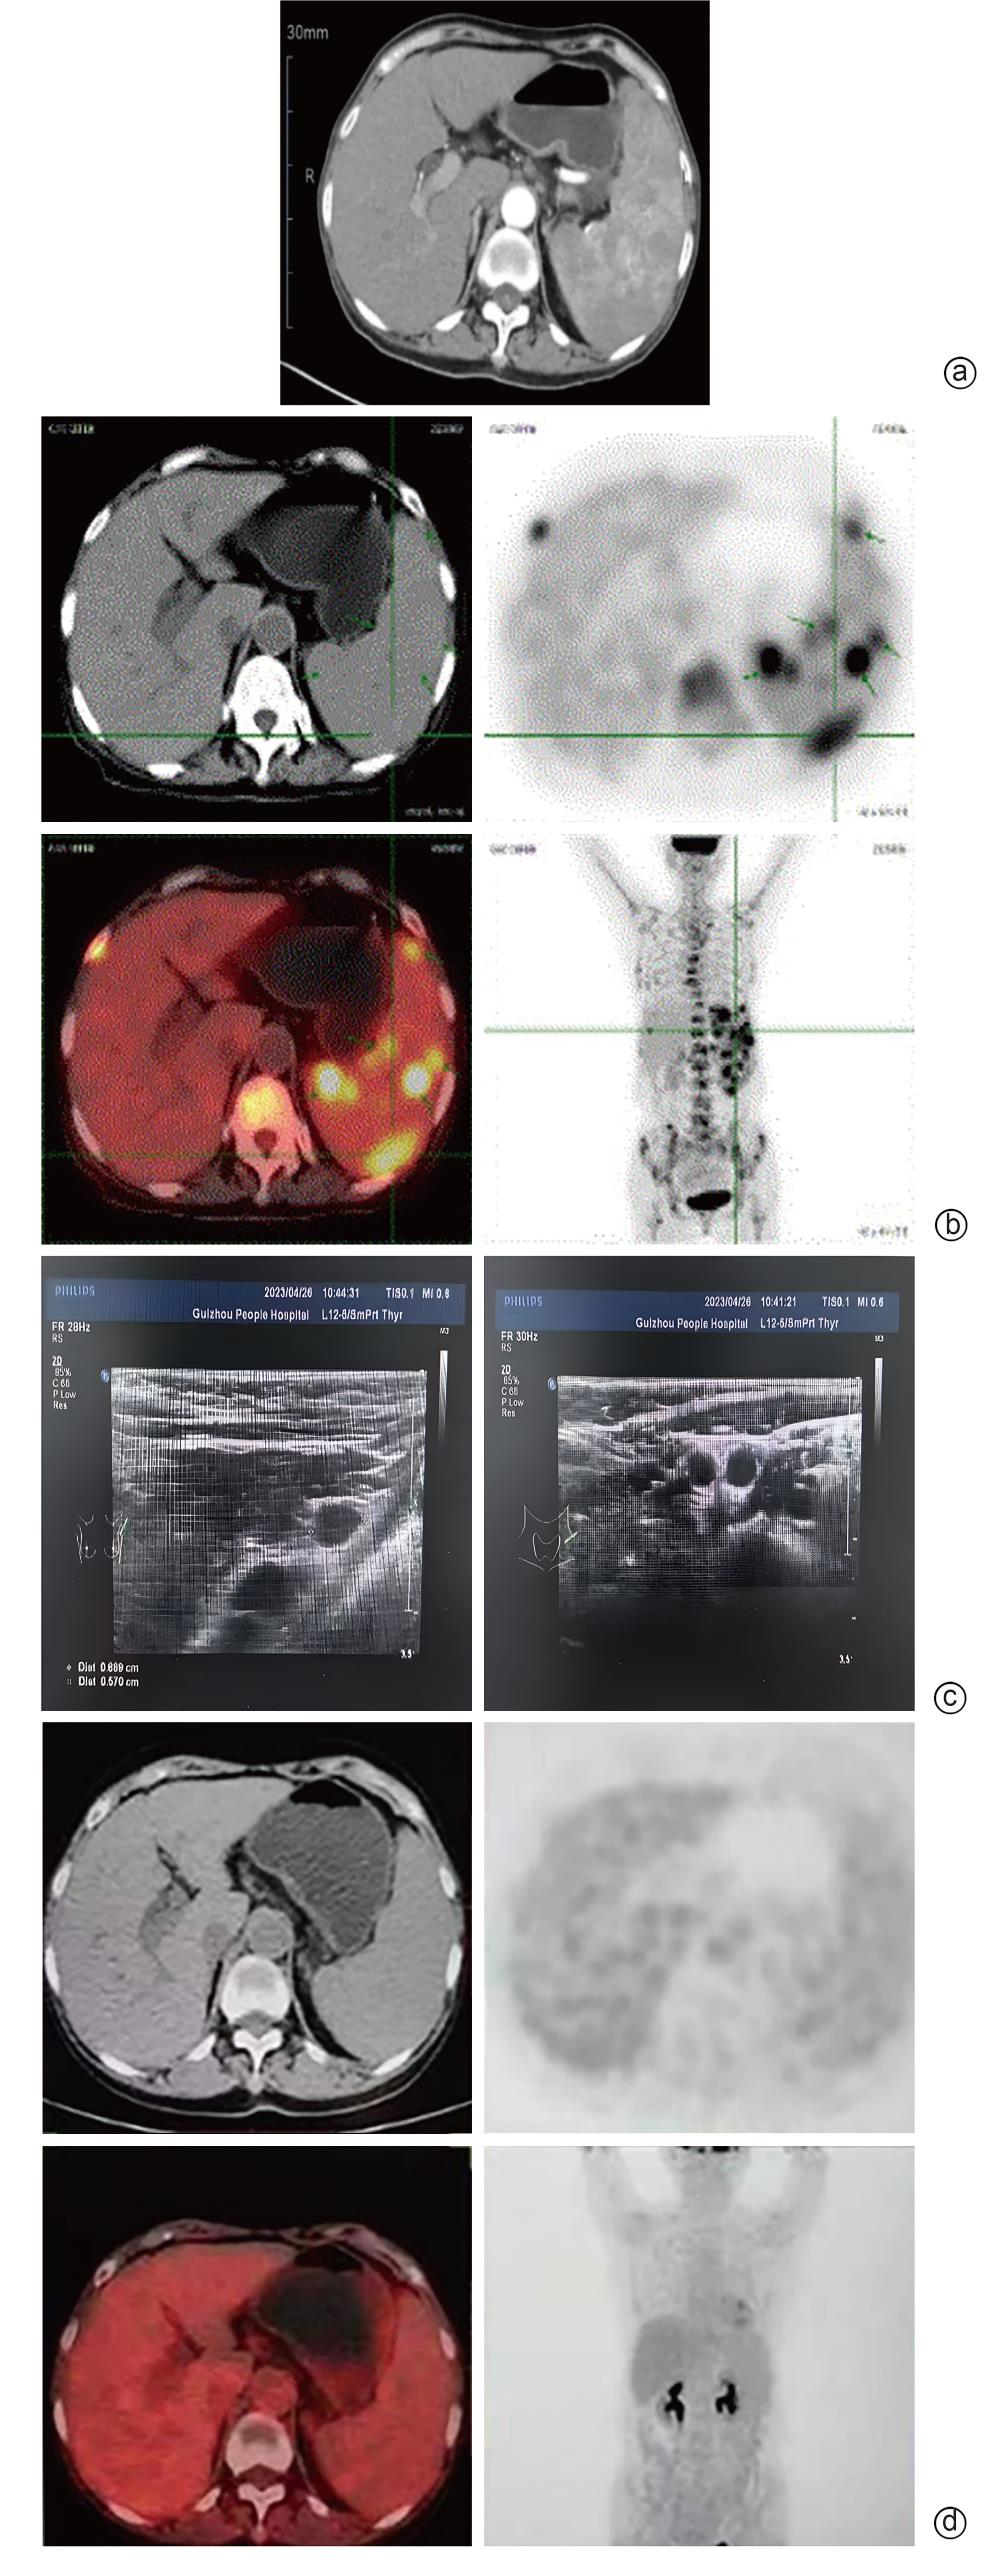

Primary splenic lymphoma misdiagnosed as Sjögren’s syndrome with liver cirrhosis: A case report

Chengcheng LI, Yuhong LIU, Lu WANG, Hong PENG, Xinhua LUO, Hong LI

2025, 41(9): 1883-1887. DOI: 10.12449/JCH250925

Abstract(464) HTML (106) PDF (5783KB)(65)

Abstract:

Primary splenic lymphoma is a rare malignant neoplasm, with similar clinical manifestations to Sjogren’s syndrome and liver cirrhosis, which often leads to misdiagnosis. This article reports a case of primary splenic lymphoma misdiagnosed as Sjogren’s syndrome with liver cirrhosis, in order to improve the understanding of primary splenic lymphoma, Sjogren’s syndrome, and liver cirrhosis and avoid misdiagnosis and treatment delay.